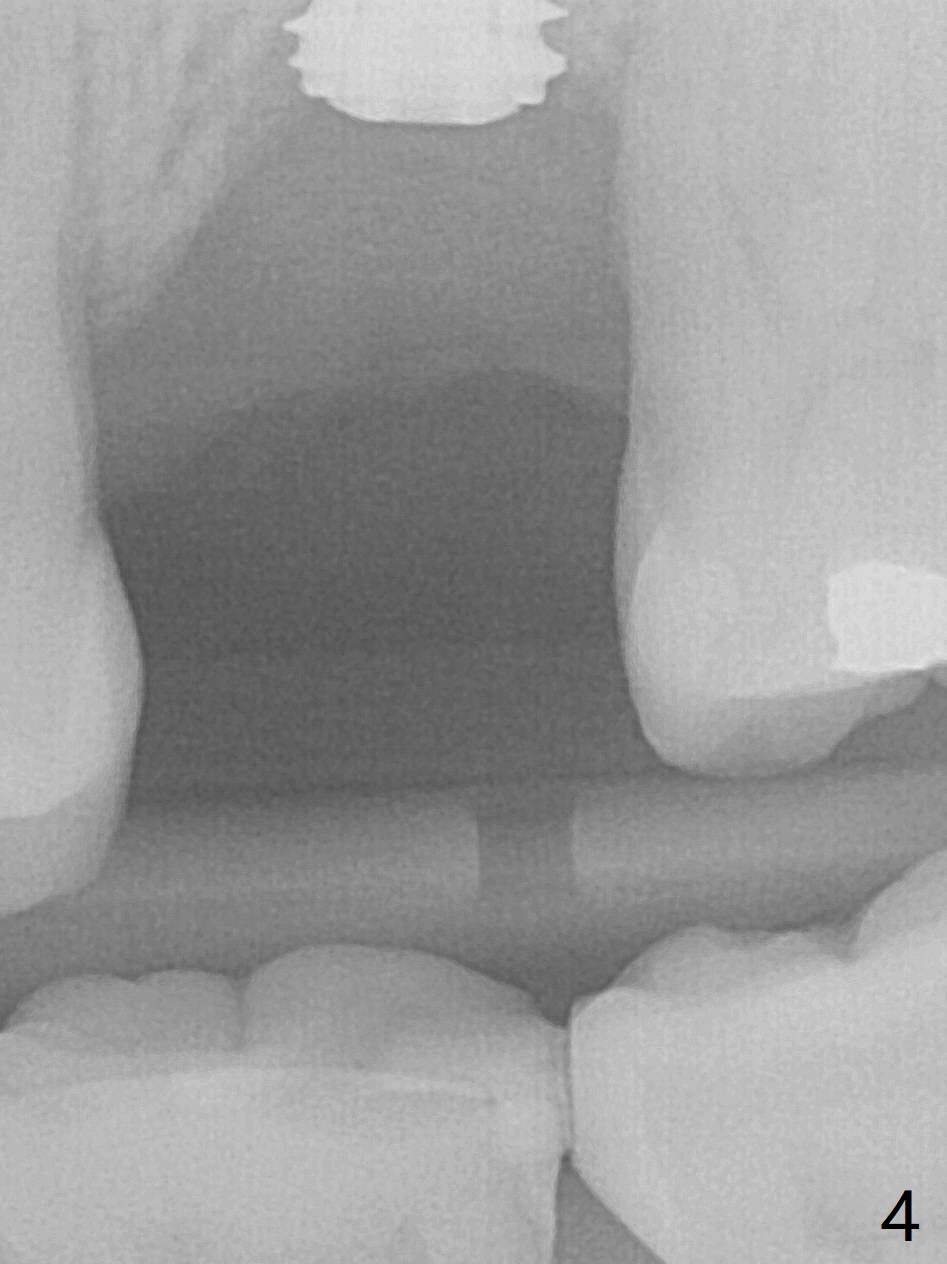

When an IBS implant with PAT surface (4.5x9 mm at #14; Fig.1 CT coronal section with ~ 7 mm bone height) is uncovered nearly 12 months postop, it is loose with a peri-implant space. Immediately post its removal and debridement, an IS dummy implant with SLA surface treatment (Fig.2: 4.5x10 mm) is placed. When a definitive implant is placed (Fig.3,4: 5x7.3 mm), it is subcrestal buccally and nearly equicrestal palatal. The remaining periimplant space is to be filled with demineralized cortical allograft. PAT: photo activated treatment (particles of calcium phosphate and a heating treatment). There is no apparent bone loss 3 months postop (Fig.5,6). The implant is uncovered with placement of a 5.7x4(4) mm cementation abutment and a nonfunctional provisional.